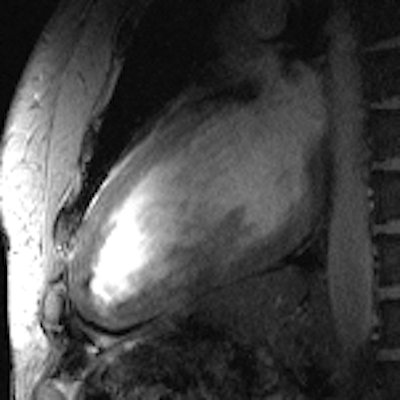

All these efforts culminated in images of the beating heart with a spatial resolution that is by a factor of five superior to that routinely available at 1.5 tesla, and which might come close to turning a 10-megapixel digital camera into a 50-megapixel digital camera. These improvements offer detailed insights into cardiac anatomy and allow accurate delineation of myocardial borders, a feature that is essential for cardiac chamber quantification.

Cine images (left: four-chamber view, middle: short-axis view, right: two-chamber view) of the beating heart acquired with a novel 16-channel transmit/receive radiofrequency coil array at 7.0 tesla with an in-plane resolution of 1 x 1 mm2 and a slice thickness of 4 mm. Images courtesy of Dr. Thoralf Niendorf.The novel technology tailored for cardiac MRI together with the quality of the anatomical and functional images have created excitement among the international imaging community during the ISMRM meeting, which ran a special session on ultrahigh-field CMR. The first clinical results and experiences are very much heartening and are the driving force for broader clinical studies.